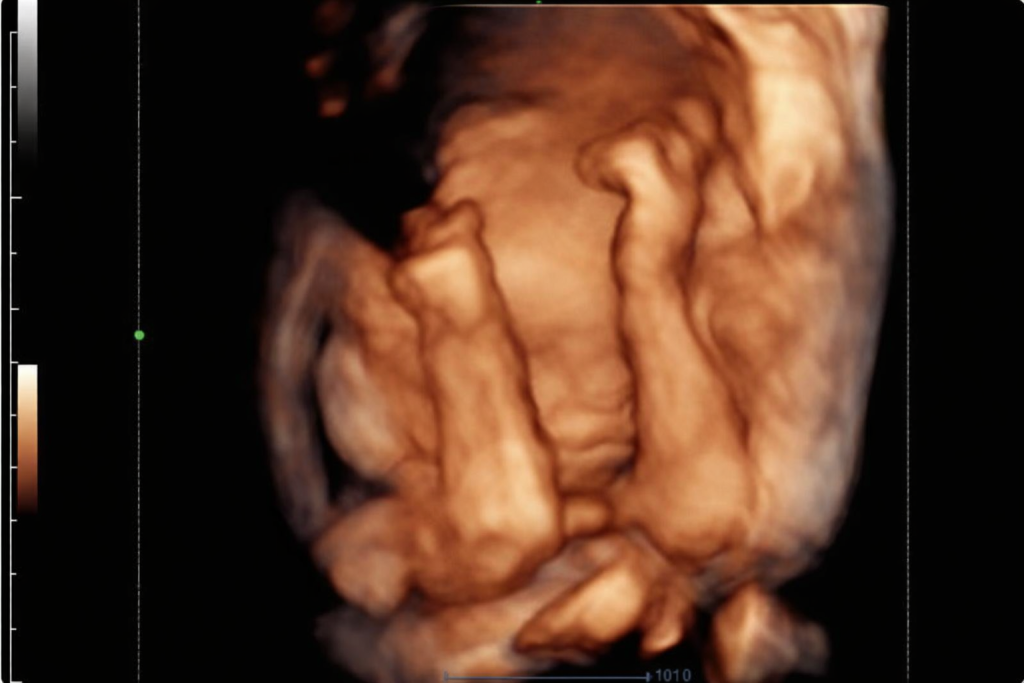

4D ultrasound scan: Bringing Movement to Life

If a 3D scan is a still photo, a 4D scan is a whole live video! The “4D” stands for “fourth dimension,” which is time. You may see your baby smiling, yawning, hiccuping, stretching, and moving hands and feet. It’s an incredibly dynamic and moving experience that offers an unparalleled bonding opportunity for you, your partner, and even excited siblings or grandparents. Imagine watching your baby’s expressions unfold right before your eyes!